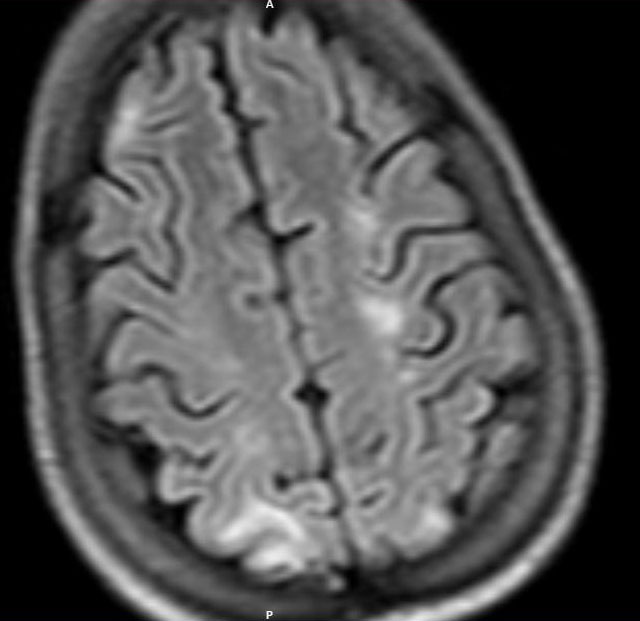

A 26 years old woman with multiple joint pain & swelling over the face & abdomen

Radiological images: